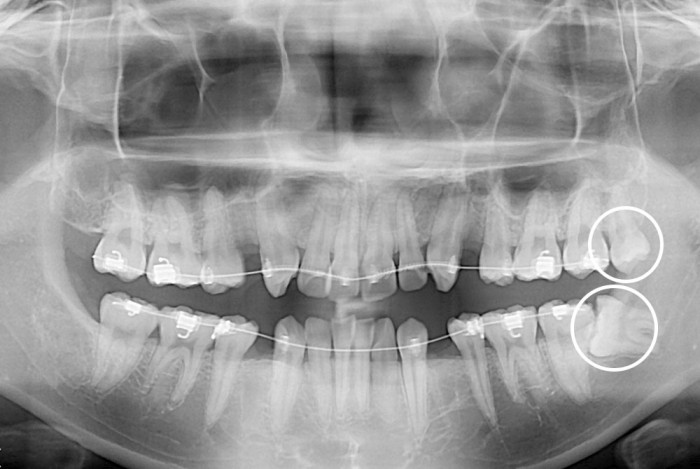

[사랑니] 사랑니

치료전 : 2019-06-19

세종치과는 구강악안면외과학 박사이신 원장님이 발치하는 치과입니다.